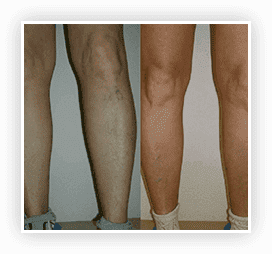

WYNIKI ZA 3,5 TYGODNIA

PRZED I PO Vasaxal

WYNIKI ZA 5 TYGODNI

PRZED I PO Vasaxal

W wyniku zastosowania krem Vasaxal z 4% kompleksu BC uzyskano następujące dane:

Szerokość centralnego naczynia zmniejszyła się o 87,8%.

Rozszerzenie sieci naczyniowej zmniejszyło się o 90%.